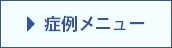

骨粗鬆症により手や足の骨折の他に、椎体(ついたい, 背骨)の圧迫骨折が起こります。

圧迫骨折は体幹部の屈曲時に動きの大きい下位胸椎から腰椎に好発します。

局所麻酔下で皮膚から椎体に針を刺し、骨セメントを注入することにより、椎体を内部から固定する方法です。